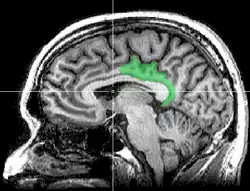

![]() Sagittal MRI slice with highlighting indicating location of the posterior cingulate | |

The posterior cingulate cortex (PCC) is the caudal part of the cingulate cortex, located posterior to the anterior cingulate cortex. This is the upper part of the "limbic lobe". The cingulate cortex is made up of an area around the midline of the brain. Surrounding areas include the retrosplenial cortex and the precuneus.